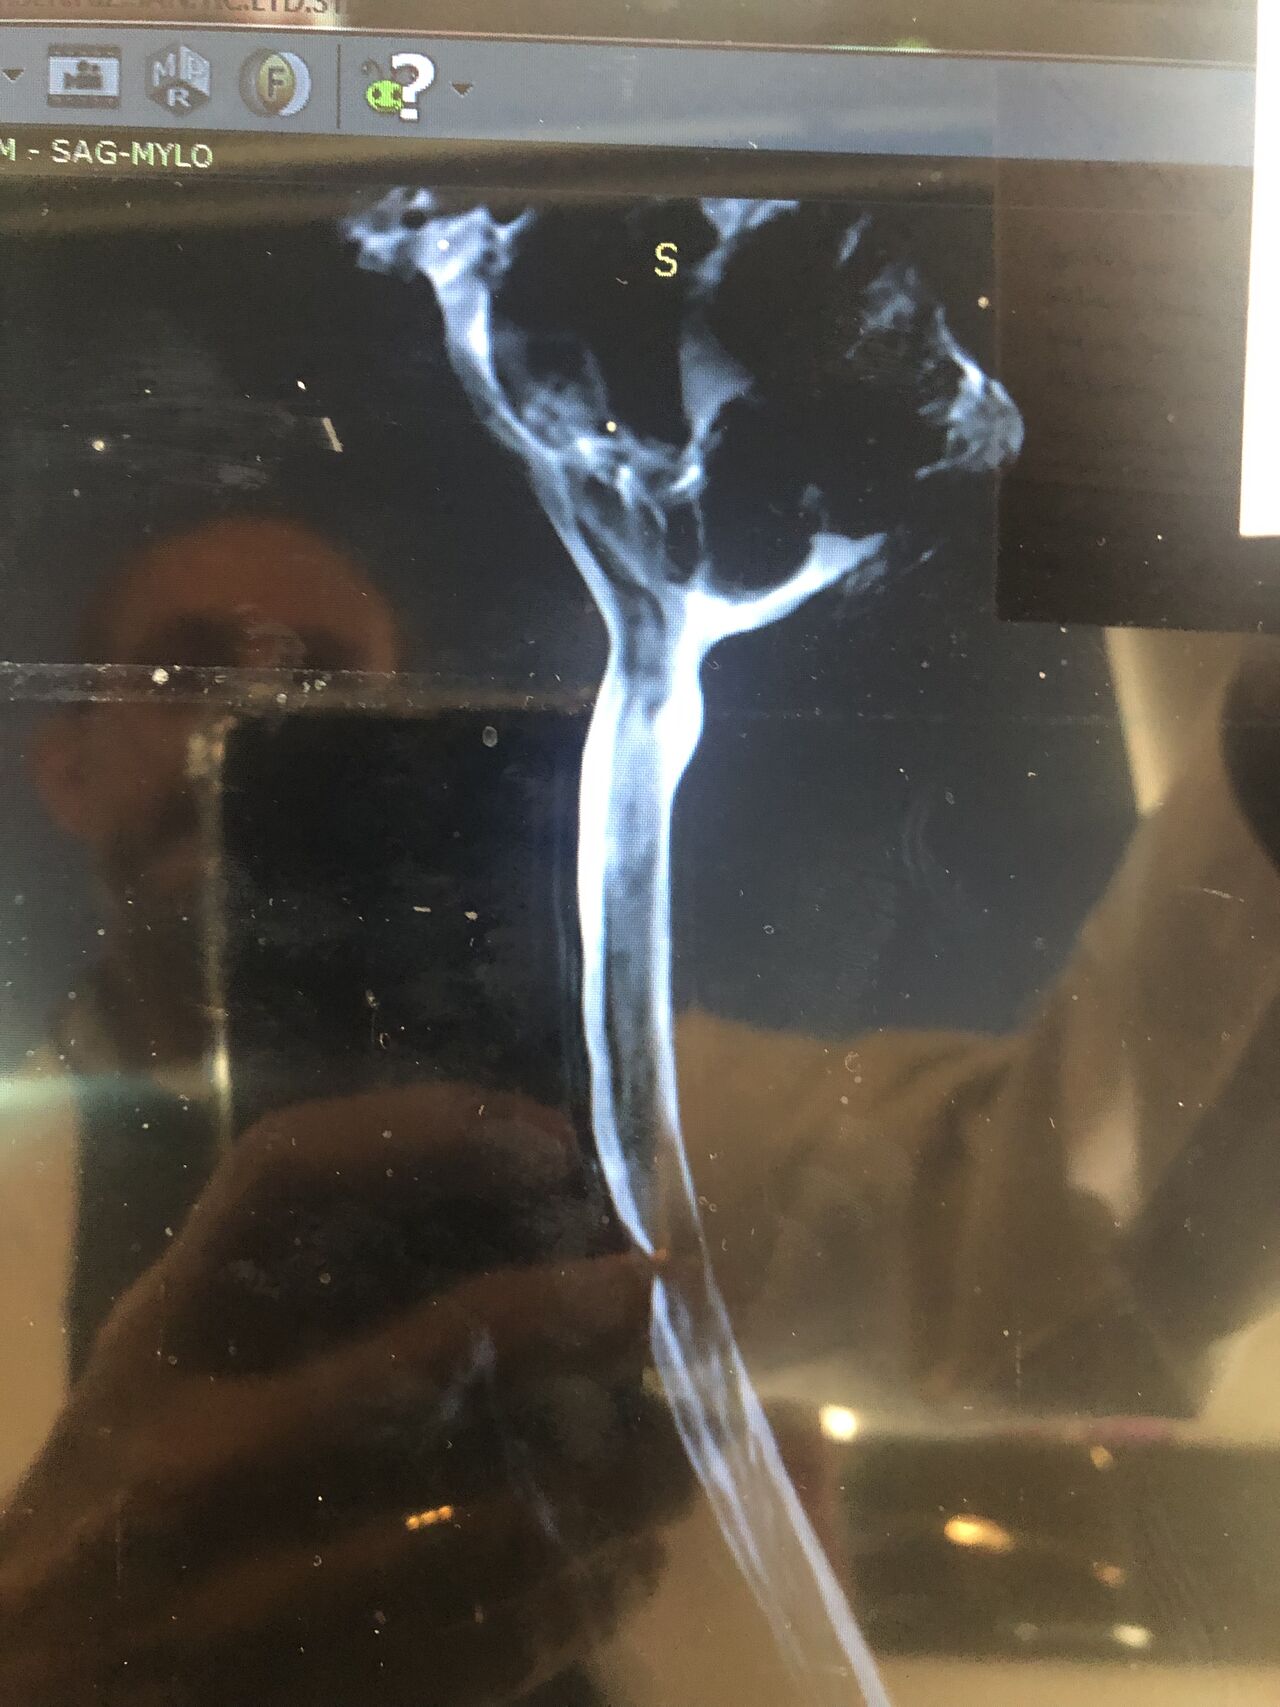

41 years old man presented to my clinic in October 2023 with acute and sever R neck pain with radicular pain to his R upper extremity along C6 dematom since 2 weeks ago. Examination didn’t show any upper motor signs. Was suggested urgent surgery

I ordered EMG/ NCV : showed mild R C6, C7 irritation without any active axonal loss

In his MRI was reported R. para R. IVF Massive extrusion. I decided to control his pain and manage this patient with reevaluation of patient every other session. For 5 sessions i just used acupuncture and laser and IFC and mild adjustments to his R. T3-T7 and mild arthosteem to above and below involved segment. Cervical adjustment considered contraindicated for this patient. From session 6th- 8th i started to use mild/gentle cervical decompression. He used soft cervical collar all the time. His pain decreased by 80 percent

I gave him cervical traction pump to be used 3-5 times per day at home for the next 3 months and i released the patient. He was evaluated every week once for one month and after that every 2 weeks. After 3 month I repeated MRI. Size of the herniated disc was reduced greater than 50 percent. Asked him to do another mri in 6 months

In general: Precise selection of the patients, examination,diagnosis, plan of management, reevaluation and treatment can be done by doctors of chiropractic for the patients with spinal disc herniation and stenosis Moreover giving reasonable time to these kind of patients under direct supervision by their chiropractic doctors can prevent unnecessary surgery. Proper selection of these kind of patients is another important fact that can be done precisely by chiropractors.

MRIs before and after proper management of this patient: